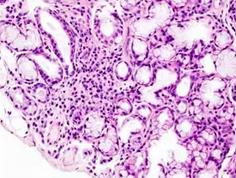

结缔组织由细胞和大量细胞间质构成,结缔组织的细胞间质包括液态、胶体状或固态的基质、细丝状的纤维和不断循环更新的组织液,具有重要功能意义。细胞散居于细胞间质内,分布无极性。一般所说的结缔组织仅指固有结缔组织,结缔组织在体内广泛分布,具有连接、支持、营养、保护等多种功能。

结缔组织病是以疏松结缔组织粘液样水肿及纤维蛋白样变性为病理基础的一组疾病。临床工作中常见的包括系统性红斑狼疮、类风湿关节炎、皮肌炎、结节性多动脉炎、白塞氏病等。其常常表现为全身结缔组织受累,其中消化系统症状首发较为常见。